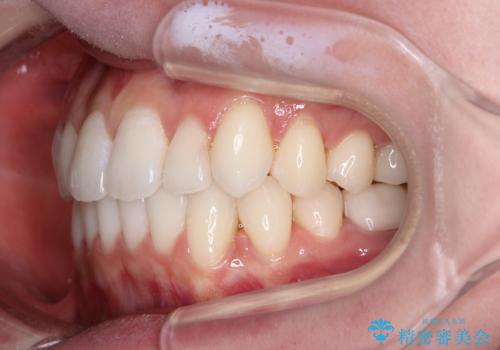

ワーキングホリデー前にきれいな歯列に

- 2、3年後にワーキングホリデーで海外に行くため、その前に歯列やむし歯をきれいにしたいとのことで来院された患者様です。

抜歯の必要な右上の奥歯は事前に抜歯をし、インビザラインにて上下歯列を整えることとしました。

矯正治療後半に奥歯の補綴治療が必要な歯にはオールセラミッククラウンを装着し、インビザラインで最終的に仕上げることとしました。

海外に行く前に口腔内環境を整えることができ、患者様には大変満足していただきました。